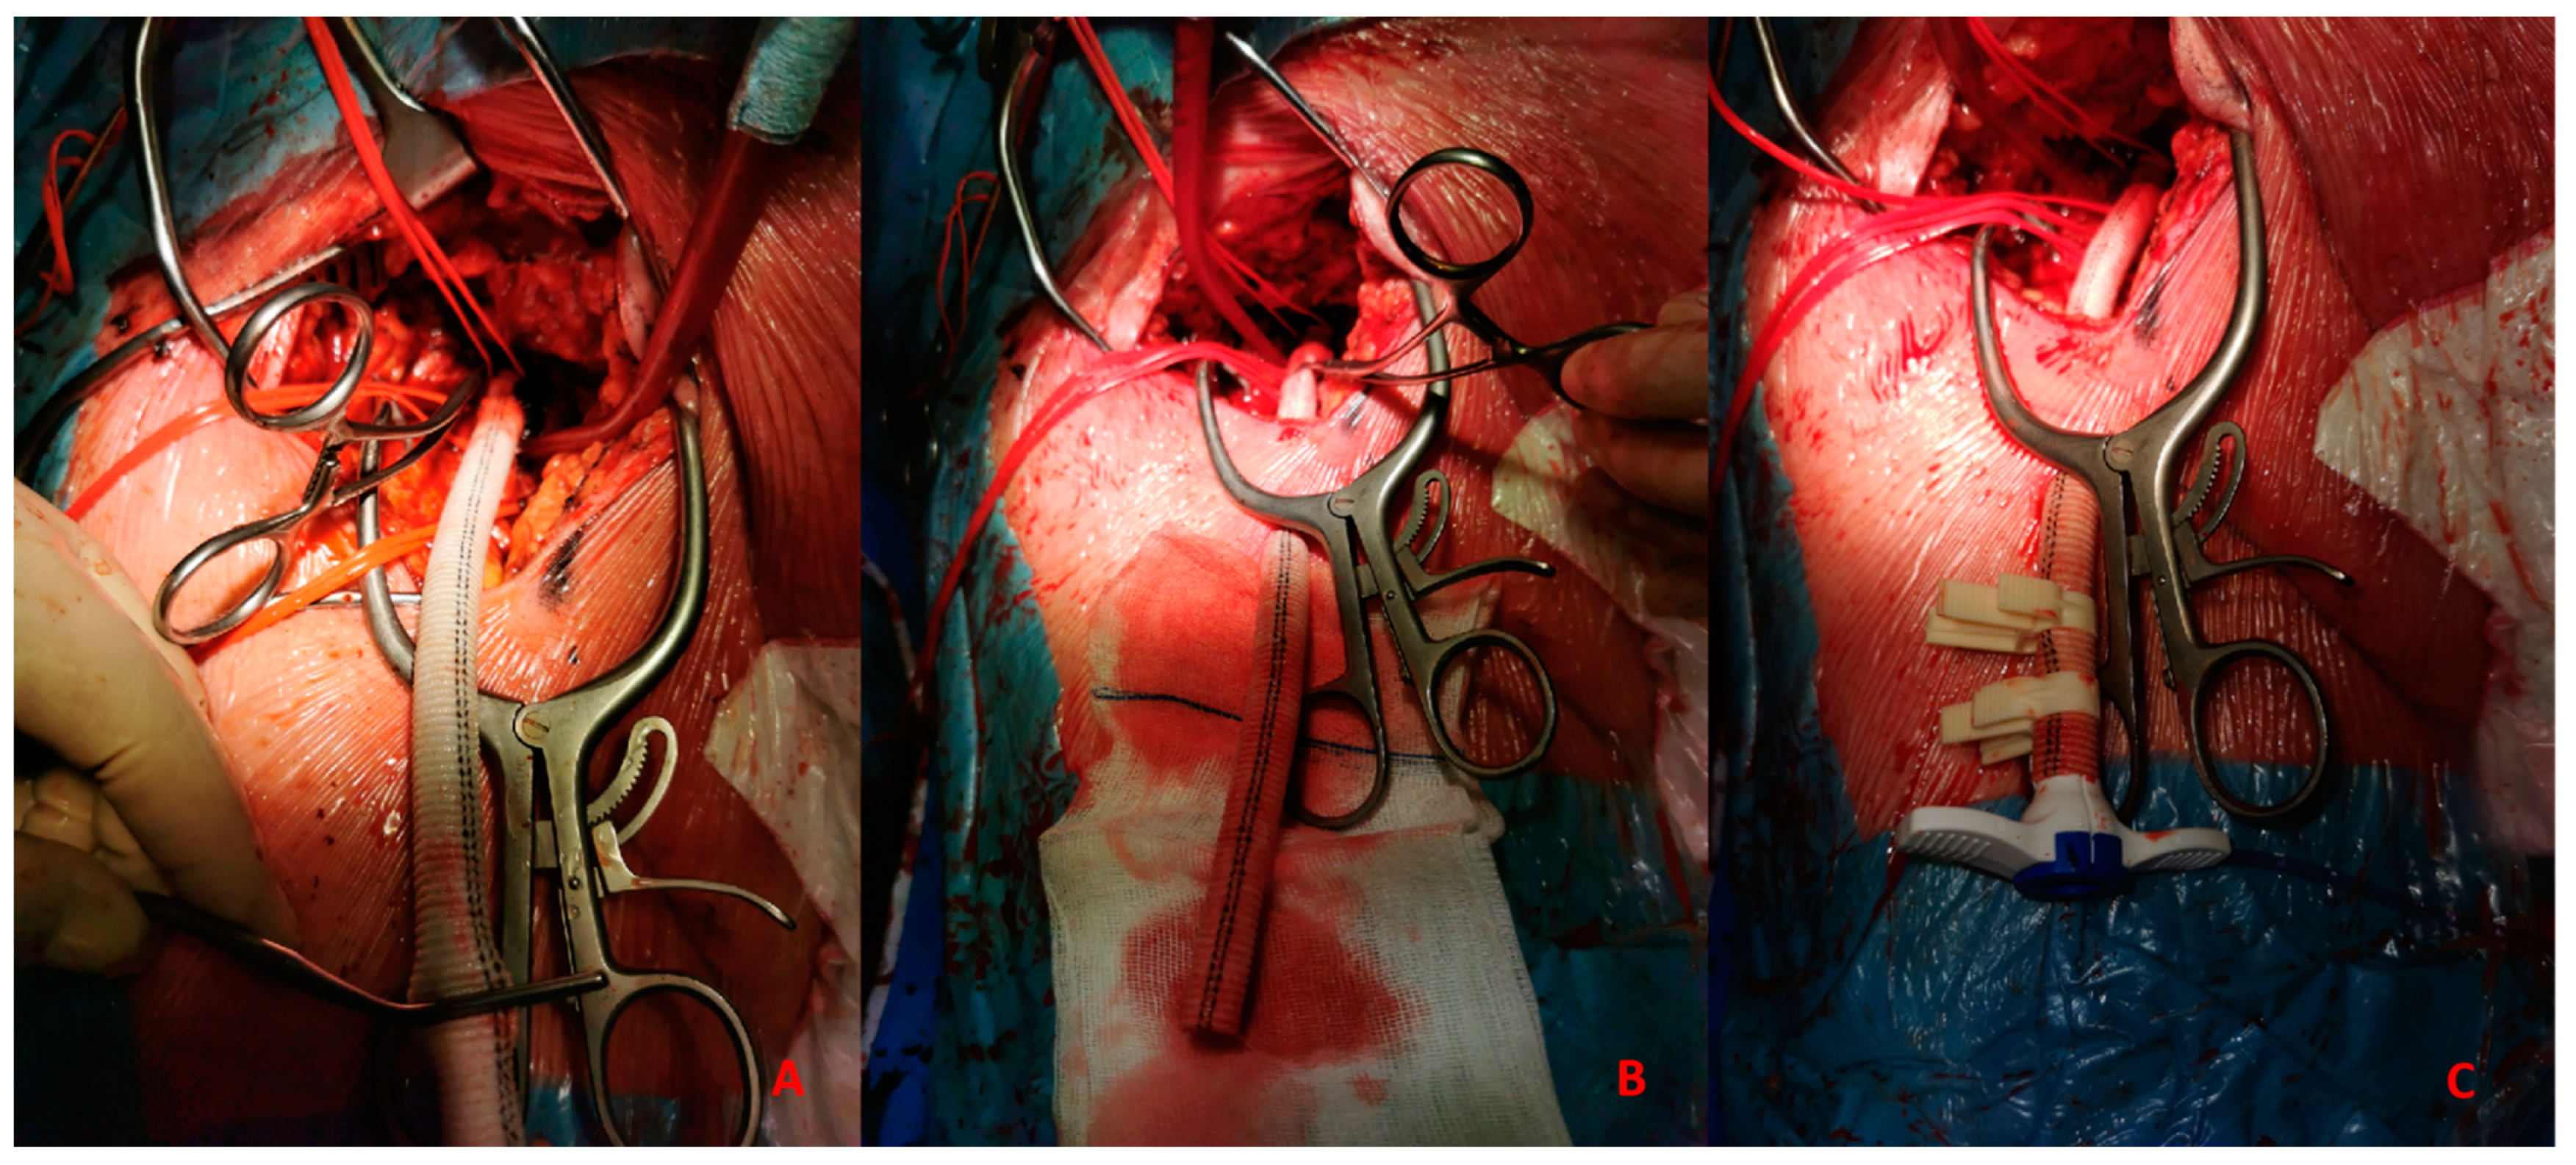

- Surgical: This approach is usually preferred in select cases, such as extremely obese patients. The surgical approach could be performed to expose the artery and the subsequent “de visu” puncture Figure 4. Moreover, a vascular graft can be anastomosed to the CFA with the insertion of a short sheath in the conduit.This approach includes six different steps:

- HR-PCI: This is often a stable situation, so a full evaluation of the access with angio CT is recommended. If the femoral route is available in patients older than 75 y, the use of IABP is often the best option; the puncture should be performed with DSA road mapping or ultrasound, and hemostasis can be obtained with a single Proglide or with manual compression. If the patient is younger than 75 y, Impella CP or VA-ECMO could be the best option. In the first case, puncture should be performed (using angio CT) with ultrasound, and the management of vascular access is easily obtained with 2 Proglide, 1 Proglide and 1 AngioSeal or Manta.In the second case the surgical approach is often necessary. If the transfemoral route is not available, PCI without support could be an option for patients older than 75 y. Otherwise, the surgical approach (surgical cutdown of femoral access, TA or TC) is a feasible option with the support of a cardiac or vascular surgeon.